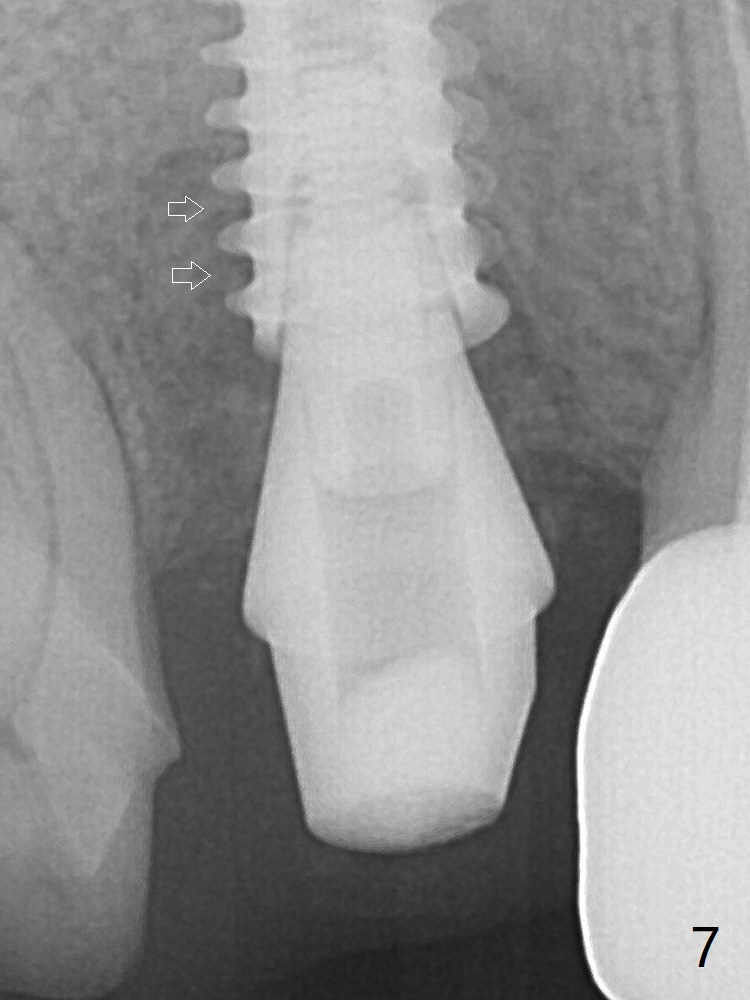

To reduce the gap and periimplantitis, a 5x11 mm IBS implant is placed with insertion torque > 50 Ncm after further osteotomy using Magic Drills (Fig.4). Following placement of 5.5x4(4) mm abutment (A), a splinted provisional is fabricated at #3 and 4. The provisional is stable 3 months postop (Fig.7). Bone graft appears to remain between the implant fins (arrows). The bone density of the bone graft between the implant fins increases 4.5 months postop (Fig.9). The bone density appears to reach the normal value (same as that of the nearby bone) 1 year 3 months post cementation (Fig.11).